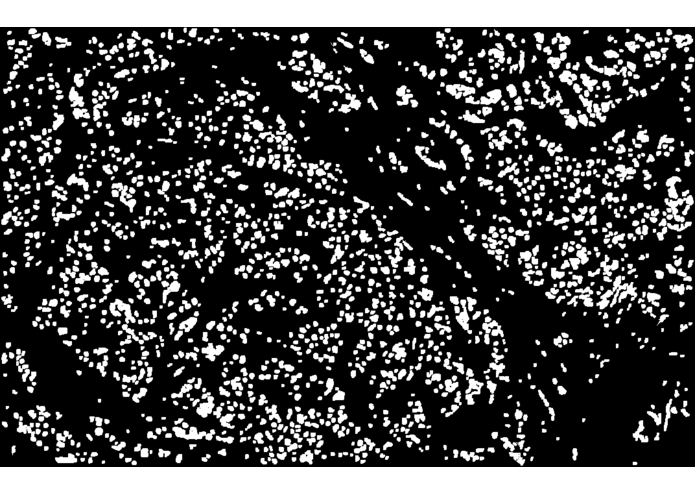

I used support vector machines (SVM) to develop a machine learning model that accurately predicts whether a breast cancer patient is likely to experience a recurrence after treatment. The prognosis method examines the patient's biopsy slide image with computer vision and leverages complex statistical methods to analyze the expression values of thousands of genes.